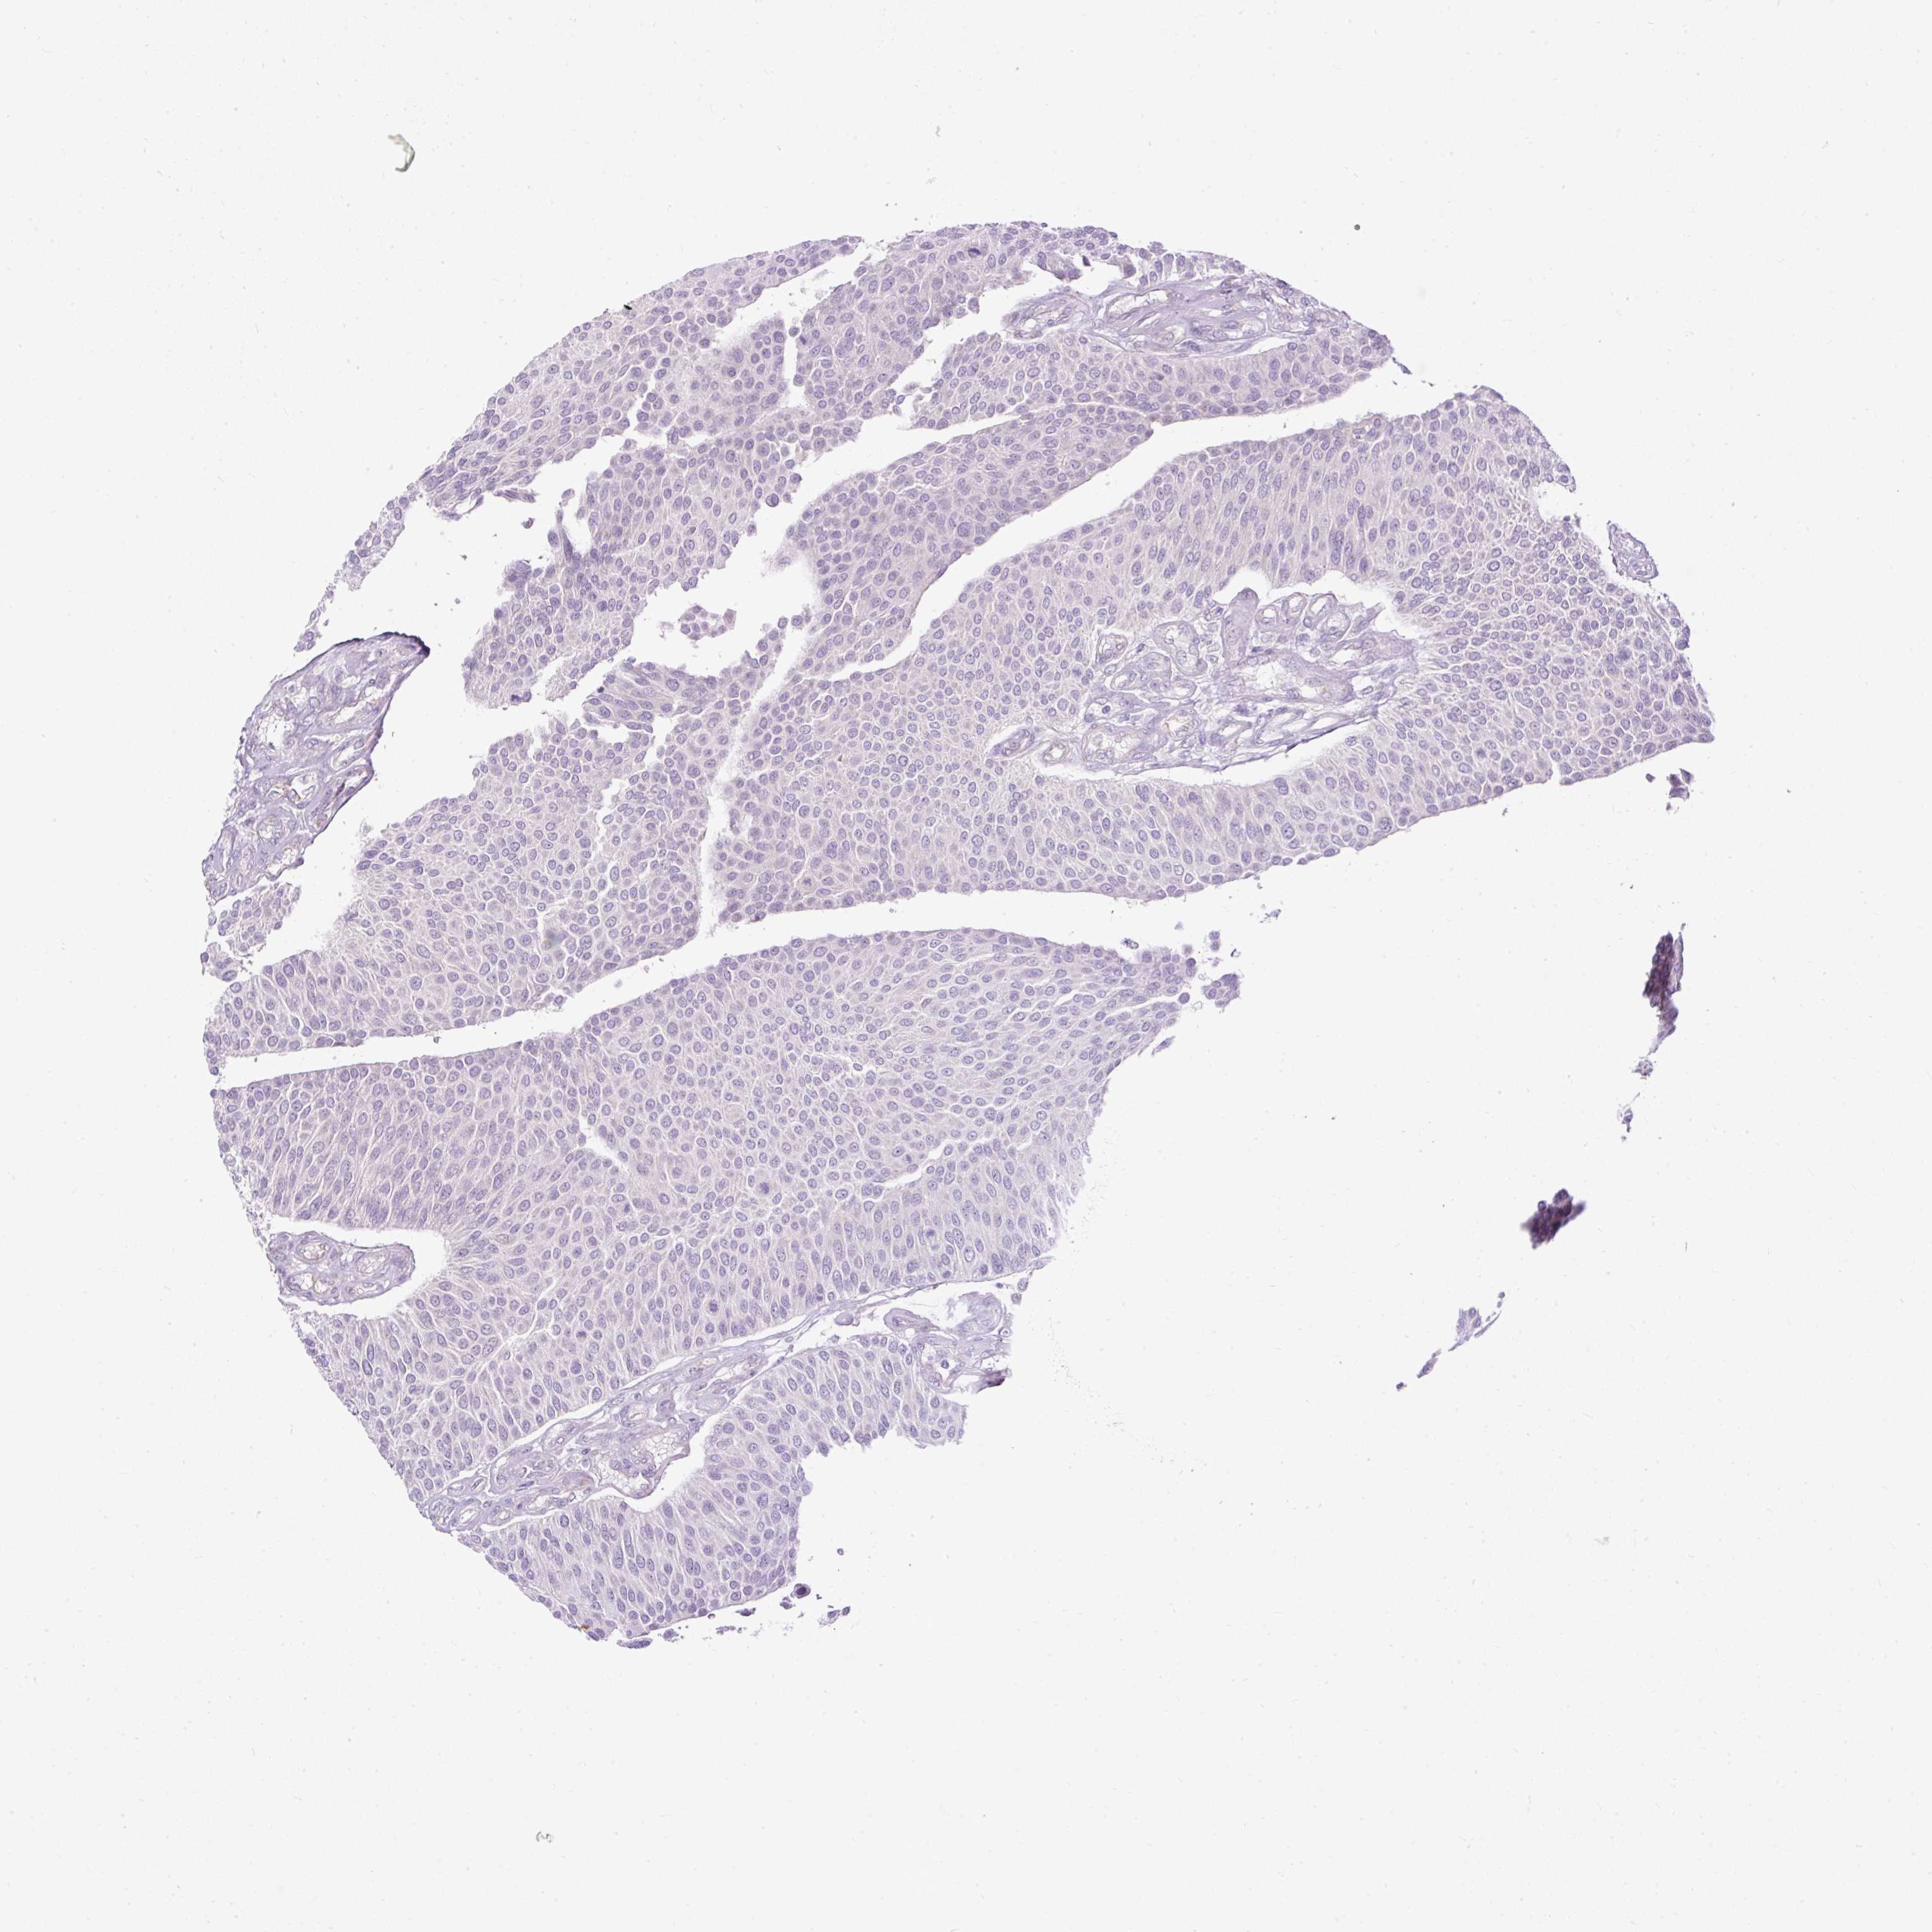

UROTHELIAL CANCER - Protein expressioni

A mouse-over function shows sample information and annotation data. Click on an image to view it in a full screen mode. Samples can be filtered based on level of antibody staining by selecting one or several of the following categories: high, medium, low and not detected. The assay and annotation is described here.

Note that samples used for immunohistochemistry by the Human Protein Atlas do not correspond to samples in the TCGA dataset.

Antibody stainingi

Antibody staining in the annotated cell types in the current human tissue is reported as not detected, low, medium, or high, based on conventional immunohistochemistry profiling in selected tissues. This score is based on the combination of the staining intensity and fraction of stained cells.

Each image is clickable and will lead to virtual microscopy that enables deeper exploration of all samples and also displays staining intensity scores, fraction scores and subcellular localization as well as patient and tissue information for each sample.

Antibody HPA045663

Antibody HPA051631

Staining

High

Medium

Low

Not detected

Intensity

Strong

Moderate

Weak

Negative

Quantity

>75%

75%-25%

<25%

None

Location

Nuclear

Cytoplasmic/membranous

Cytoplasmic/membranous,nuclear

Urothelial carcinoma, Low grade